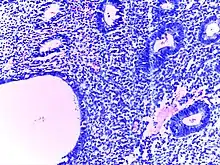

![]() | Diffuse B-cell lymphoma | Lymph node FNA specimen showing diffuse large B cell lymphoma. | Category: Histopathology of diffuse large B cell lymphoma | Diffuse large B-cell lymphoma |

![]() | Follicular lymphoma | Micrograph showing a small B-cell lymphoma compatible with follicular lymphoma. H&E stain. | Category: Histopathology of follicular lymphoma | Follicular lymphoma |